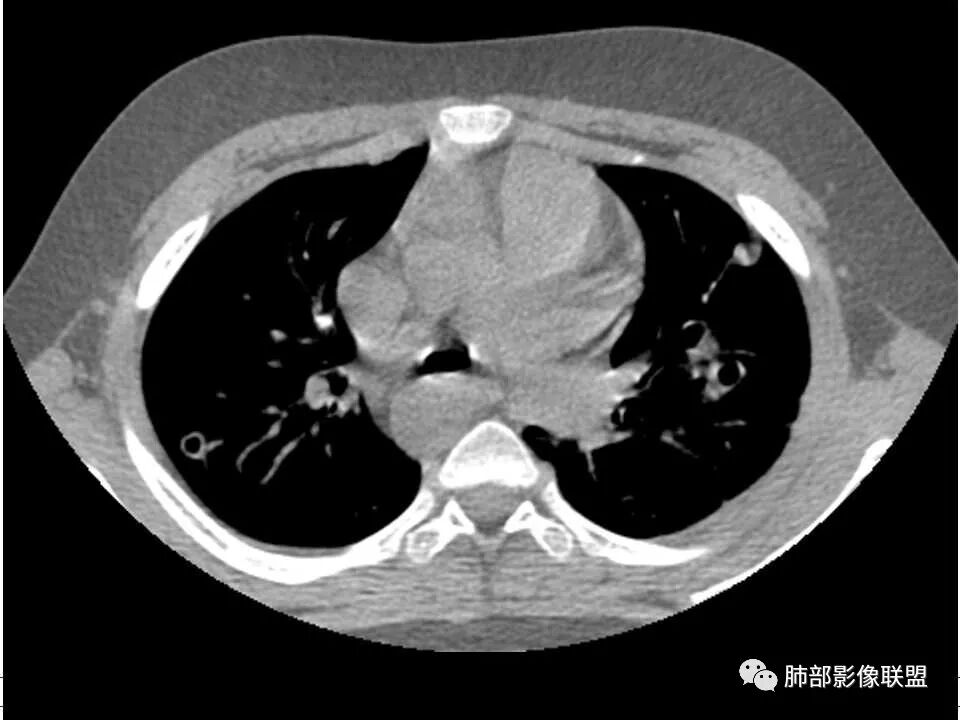

发热,下肢肿胀骨髓水肿,骨髓炎可能;双肺多发结节,部分空洞,左下肺胸膜下楔形阴影,考虑感染性病变,肺梗死;上腔静脉、奇静脉增宽,肝大,考虑股部深静脉拴子进入体循环及肺动脉,综上考虑下肢骨髓炎,深静脉脓毒栓子,肺部感染并肺栓塞

2.双肺多发片影,随机分布,多空洞或囊腔,胸膜下多楔形影,气道未见受累等等符合脓毒血症影像学表现,尤其是金葡。

2、脓肿:实变区内脓肿,最常见吸入性金葡菌引起的多,下叶多见,在实变区中央,外壁不清,内壁光滑,可见气液平面;血源性脓肿,多发,结节状,大小无差异,边清,光滑,壁薄;